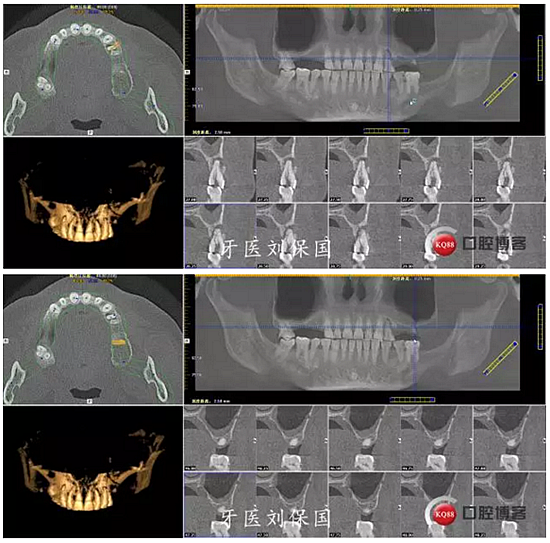

1.術前CT: